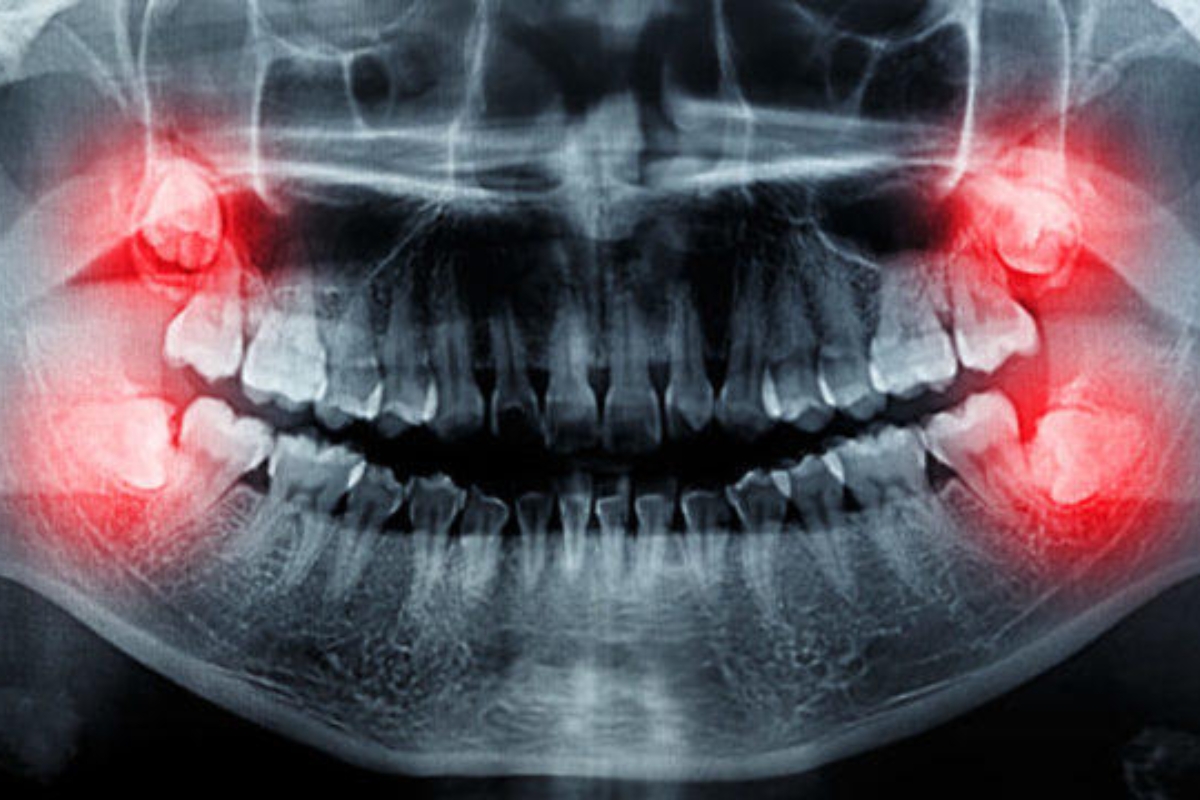

- Pre-Operative Assessment: Your oral surgeon will evaluate your teeth and may take X-rays to plan the best approach for the extraction.